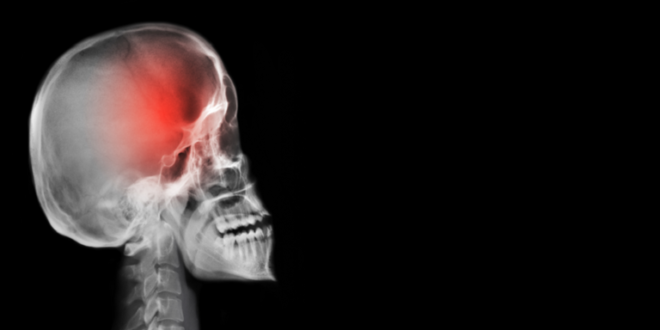

6 أعراض قد يشير ظهورها إلى وجود ورم في المخ

تعتبر أورام الدماغ واحدة من أكثر أشكال السرطان فتكا، ولكن لا يعرف الجميع علاماتها الأساسية.

وتعتمد الأعراض على مكان تواجد الأورام في الدماغ، وغالبا ما يمكن تفويتها في المراحل المبكرة من المرض، عندما يكون العلاج أسهل، حيث يمكن بسهولة الخلط بينها وبين حالات أخرى، لذلك من المهم معرفة ما يجب الانتباه إليه.